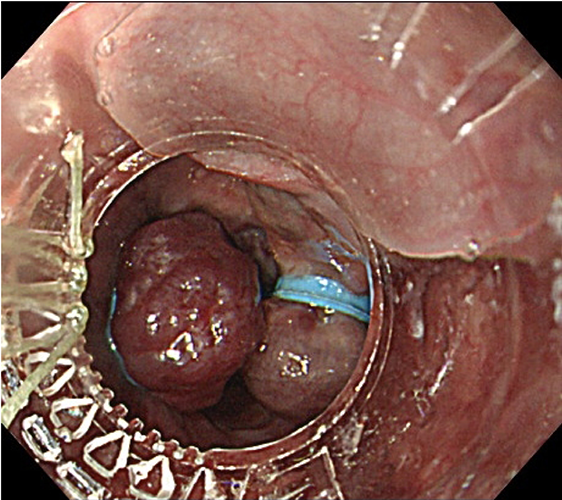

内視鏡的静脈瘤結紮術(EVL)

出典

img

1: 著者提供